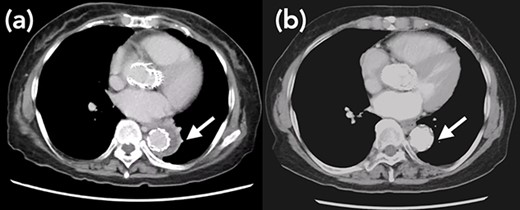

A 76-year-old woman with a giant retroperitoneal tumor was scheduled for surgical resection (Fig. 1). However, preoperative examination revealed severe aortic valve stenosis (AS); therefore, the patient first underwent minimally invasive aortic valve replacement (MICS-AVR) for severe AS. In this operation, we approached the surgical site through the right third intercostal space, and cardiopulmonary bypass was established with right femoral arterial and venous cannulation. PERCEVAL (Livanova, London, UK), a sutureless valve, was used as the artificial valve. Five days post-operatively, she complained of back pain, and a computed tomography (CT) scan revealed bleeding in the tumor and tumor growth. There were no findings of aortic dissection. A peripheral branch of the left third lumbar artery seemed to be the bleeding site; thus, lumbar artery transcatheter artery embolism (TAE) was performed. Although the bleeding stopped, early surgery was considered to be appropriate for the tumor. Therefore, retroperitoneal tumor resection and left nephrectomy were performed on the 12th post-operative day. Four days after tumor resection, the patient suddenly experienced persistent back pain again. CT revealed a Type B AAD. The aorta was dissected from the distal part of the left subclavian artery (LSA) to the level of the right renal artery, and an ulcer-like projection (ULP) was observed at the distal arch (Fig. 2). Although conservative treatment was started immediately, her back pain persisted and follow-up CT revealed slight growth of the ULP. Thus, we decided to perform thoracic endovascular aortic repair (TEVAR) using Valiant (Medtronic, Minneapolis, USA). Before the TEVAR procedure, we performed extra-anatomical bypass from the left common carotid artery to the LSA using PROPATEN (Gore, USA). The Valiant was deployed from Zone2 to just above the celiac artery (Fig. 3). The post-operative course was uneventful, and the patient was discharged without any complications. One year after discharge, CT showed that the aorta was remodeled almost as before (Fig. 4).

Arrow shows false lumen. (a) One week after TEVAR. False lumen still remains. (b) One year after TEVAR. False lumen has almost disappeared.